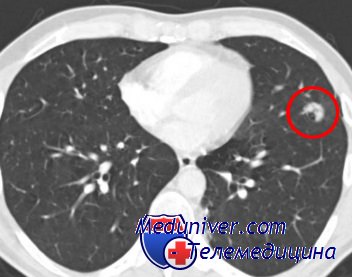

Весьма актуальной является задача организации дальнейшего медицинского обслуживания больных с нетуберкулезной патологией, выявляемых в результате комплексного дифференциально-диагностического обследования туберкулезными учреждениями. Наиболее сложной является организация лечения больных с опухолями легких и хроническими воспалительными заболеваниями. Здесь существуют самые разноречивые мнения.

Одни высказываются за передачу наблюдения и лечения больных с неспецифическими воспалительными заболеваниями легких противотуберкулезному диспансеру, другие придерживаются диаметрально противоположной позиции, предлагая передавать всех больных с нетуберкулезной патологией в ведение поликлиник. Мы считаем, что тесный и деловой контакт флюорографической службы и туберкулезных учреждений позволит увеличить процент больных, выявляемых Бранней стадии заболевания.

В Центральной туберкулезной больнице за последние 5 лет прооперировано 174 больных но поводу рака и 128—по поводу хронических неспецифических пневмоний, абсцессов и ограниченных бронхоэктазов. При злокачественных заболеваниях 95% оперированных выписано в удовлетворительном состоянии; при неспецифических воспалительных заболеваниях легких— 96%.

image

Активная хирургическая деятельность по лечению хронических неспецифических воспалительных заболеваний легких и рака легкого у больных, находящихся в туберкулезных стационарах, по нашим данным, ни в коей мере не снизила активности в хирургическом лечении больных туберкулезом.